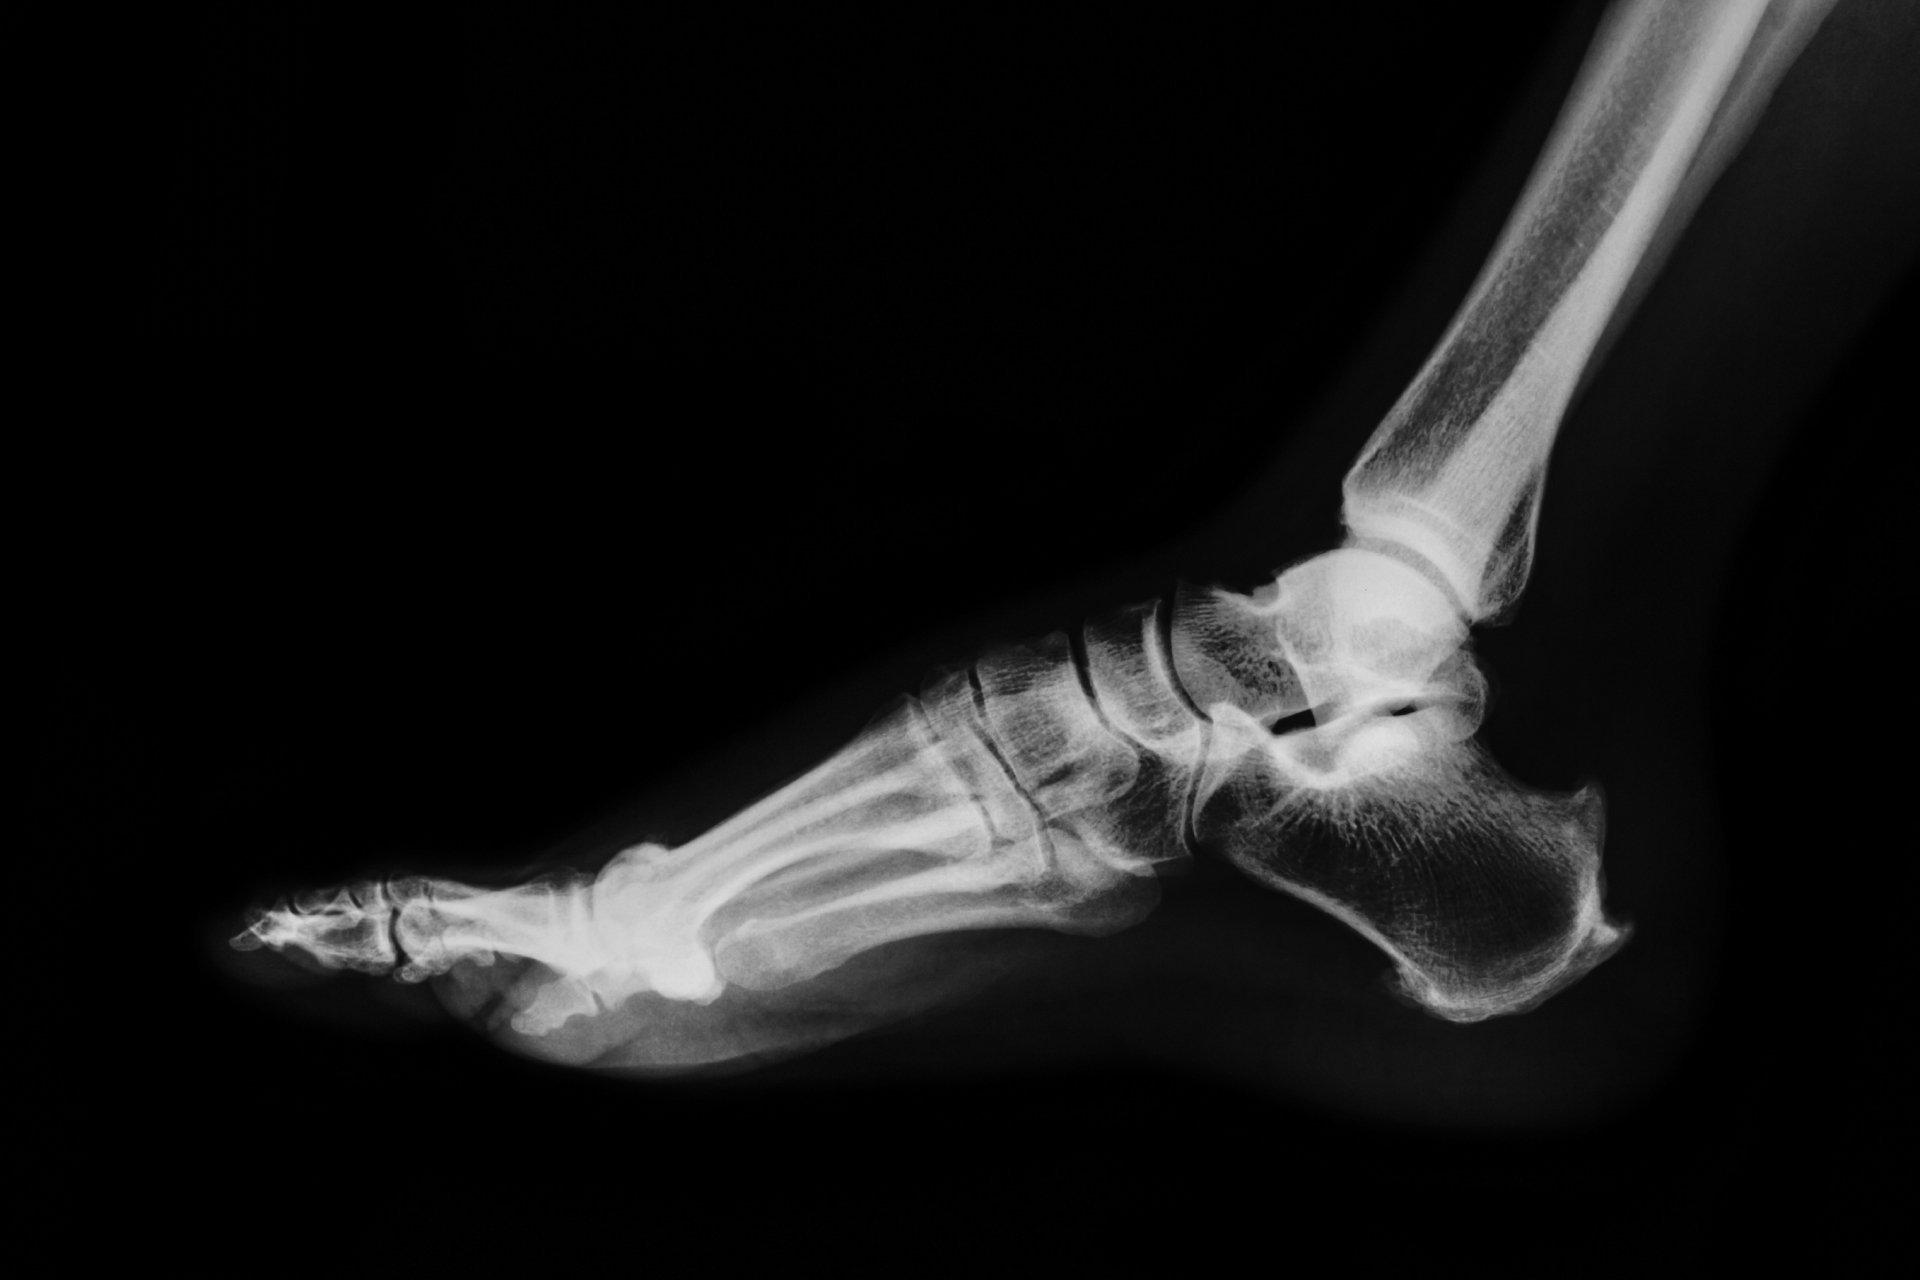

You will be cared for by numerous members of our team, working under the direction and supervision of our orthopedic surgeons. We also have the availability of on-site X-ray services and durable medical equipment supplies such as splints, slings and crutches.